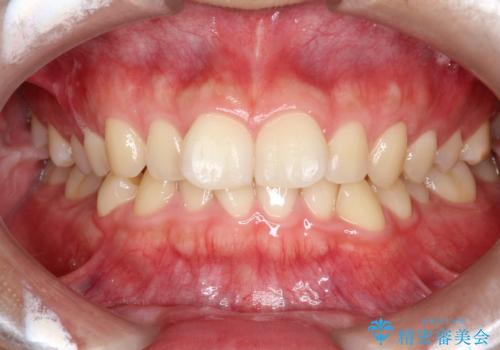

マウスピース矯正で前歯のガタツキを改善! 短期間で治療完了

- 前歯のガタツキが気になるとのことで来院されました。

マウスピース矯正で治療することとしました。